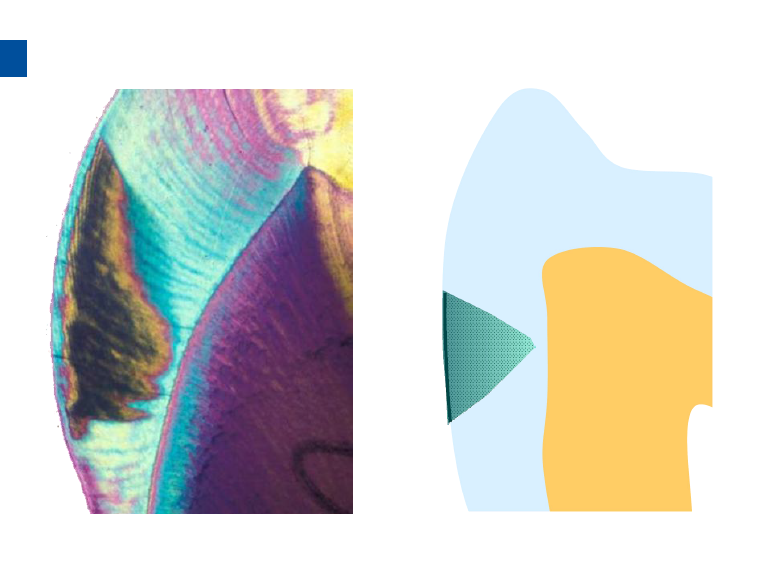

微创牙科治疗是一种全新的龋病治疗理念,着眼于疾病的早发现、早诊断、早治疗。树脂渗透治疗是介于再矿化治疗和充填治疗之间的一种创新的治疗手段,通过微量的去除牙体组织,达到加固脱矿釉质、阻止进一步脱矿的目的。

lcon渗透基于封闭釉质龋空隙的一种特殊树脂的渗透,封闭釉质龋小孔,从而阻断致龋酸传播途径,阻止龋病进一步发展。这种材料操作方法简单,对牙体组织损伤轻微,不用通过麻醉和磨切牙体来达到加固脱矿釉质,同时可以改变釉质龋表面的白色或棕色改变,达到美观修复效果,是对龋病微创治疗的突破。